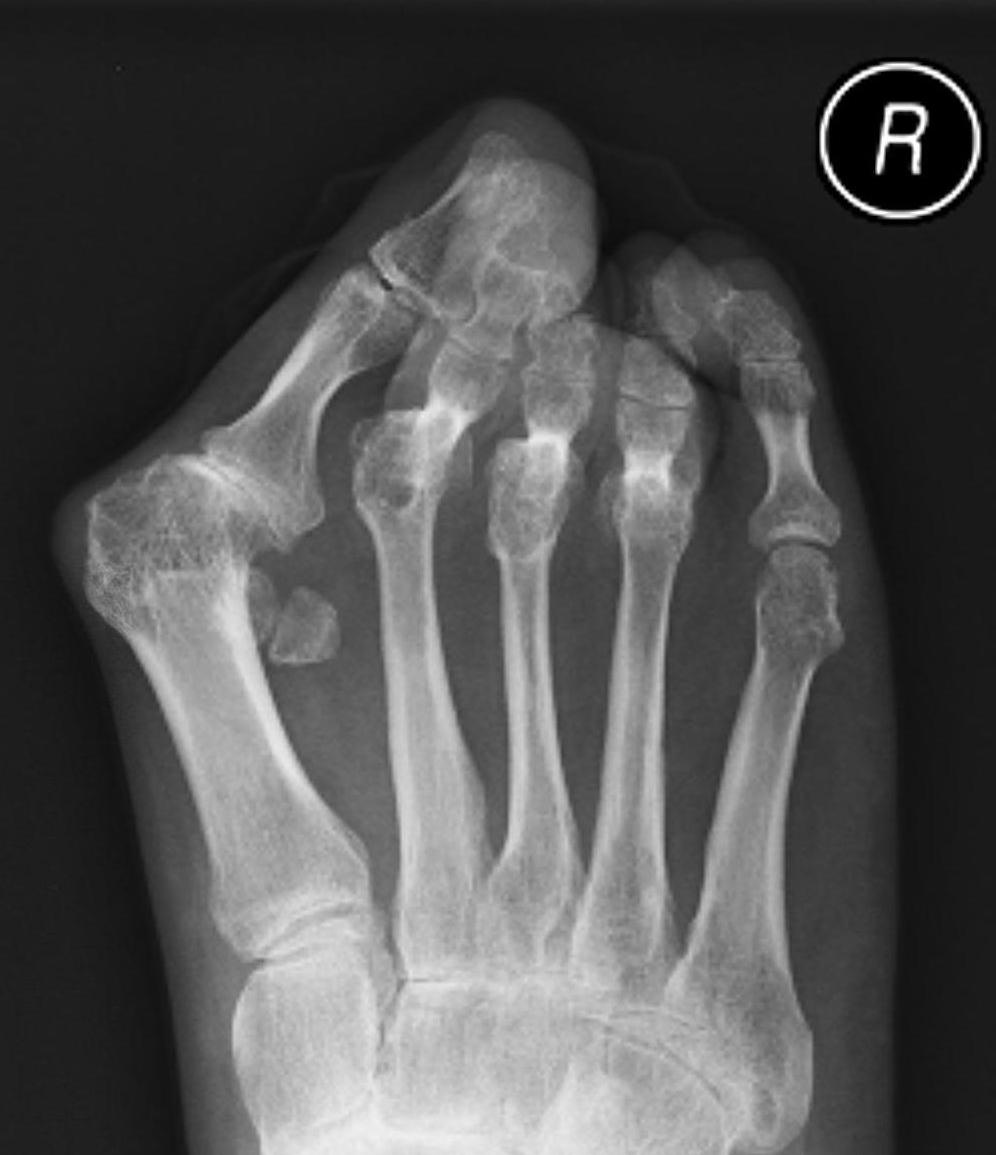

Metatarsalgia

Pathology

Synovitis of MTPJ with capsular destruction

- dorsal subluxation MTPJ

- claw toes develop (MTPJ hyperextended, PIPJ flexed)

- plantar fat pad displaced distally and metatarsal heads exposed to plantar skin

Fowler's Procedure - metatarsal head excision

Dorsal transverse skin excision just proximal to toe webs

- can be performed via transverse plantar ellipse

- with severe dislocation may be easier to approach through plantar aspect

Extensor tenotomy

Cascading excision of II - V metatarsal heads

- dorsal distal to plantar proximal

- contoured on plantar surface to give rounded surface

Claw toes